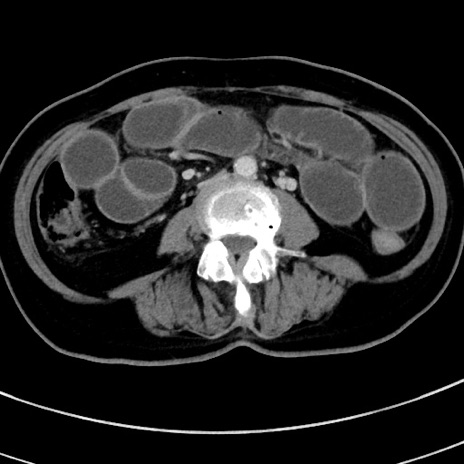

症例9(横断像)

【症例】 60歳代女性

【主訴】むかつき、みぞおちの痛み

【現病歴】3日前よりむかつきがあり、食事がとれない。

【既往歴】糖尿病

【身体所見】発熱なし、心窩部圧痛軽度あるも、腹膜刺激症状なし。

【データ】WBC 7400、CRP 1.92